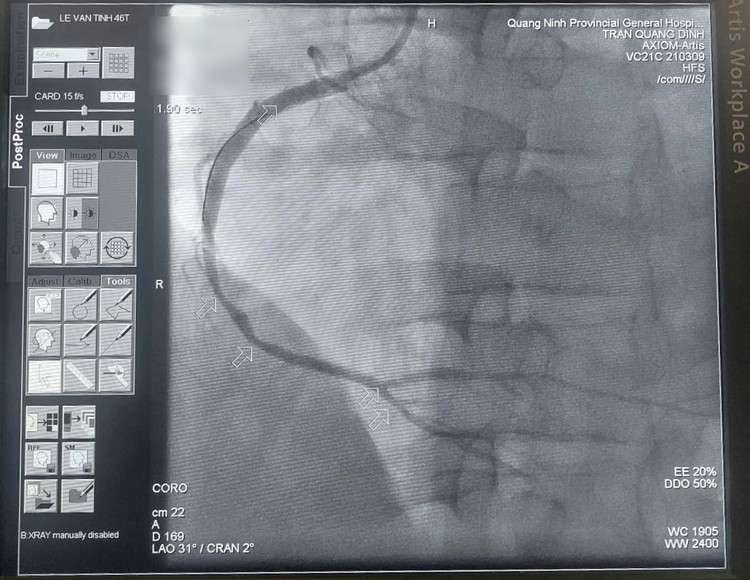

Kết quả chụp mạch cho thấy 3 thân động mạch vành tổn thương nặng, huyết khối làm tắc cấp tính hoàn toàn động mạch vành phải, động mạch mũ và động mạch liên thất trước hẹp nặng.

| Hình ảnh động mạch mũ (trái) và động mạch liên thất trước (phải) hẹp nặng. |

| Hình ảnh động mạch mũ (trái) và động mạch liên thất trước (phải) hẹp nặng - Ảnh BSCC |